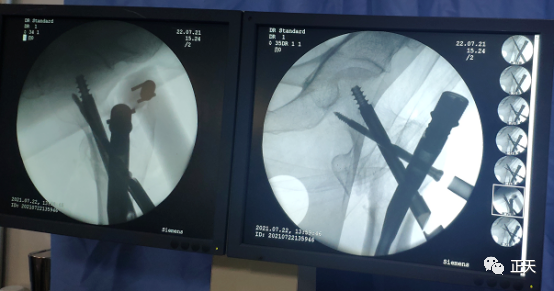

微信图片_20210801095201.png

术后透视显示骨折复位,内固定位置良好